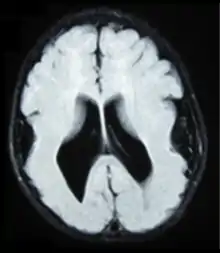

انعدام التلافيف[1] أو لدانة الدماغ[1] أو الدماغ سلس السطح (بالإنجليزية: Lissencephaly) هو مجموعة من اضطرابات الدماغ النادرة حيث يكون سطح الدماغ كله أو أجزاء منه أملس أو ناعم. كلمة Lissencephaly مشتقة من اليونانية λισσός أو lissos بمعنى "أملس"، وencephalos بمعنى "الدماغ".[2] وسبب ذلك هو هجرة الخلايا العصبية المعيبة خلال الأسبوع ال12 إلى الأسبوع ال24 من الحمل، مما يؤدي إلى نقص تطوير تلافيف وأخاديد الدماغ.[3] وهو شكل من أشكال الاضطراب الرأسي. وتستخدم مصطلحات مثل انعدام التلافيف (agyria) وضخامة التلافيف (pachygyria) لوصف مظهر سطح الدماغ. الأطفال الذين يعانون من انعدام التلافيف عموما يكون لديهم تأخر كبير في النمو، ولكن يختلف ذلك اختلافا كبيرا من طفل إلى طفل تبعا لدرجة تشوه الدماغ والتحكم في التشنجات. ويمكن أن يقل متوسط العمر المتوقع عموما بسبب مشاكل في الجهاز التنفسي.

![]() دماغ بشري أملس السطح عديم التلافيف. دماغ بشري أملس السطح عديم التلافيف. | |